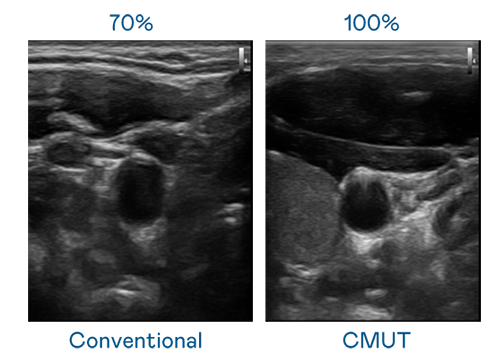

CMUT technology utilizes capacitive MEMS components to generate ultrasound signals. Compared to traditional ceramic piezoelectric technology, the 30% increased bandwidth of CMUT allows for wider ultrasound signals and greatly improved image resolution. This is a crucial technology for achieving medical ultrasounds with high-quality images and promoting the development of precision medicine.